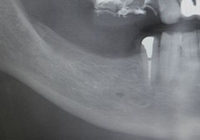

【術前の状態 】

【術後の状態 】

【術前の状態:ここは入れ歯でした 】

【インプラントを入れた後 】